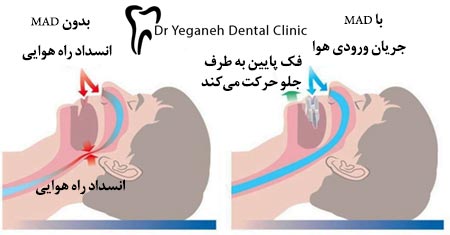

- ابزار حرکت فک پایین به جلو (MAD) شبیه به محافظ دهان هستند زیرا بر روی دهان قرار میگیرند. هر چند به جای اینکه از قرار گرفتن دندانها روی یکدیگر جلوگیری کند، فک پایین را کمی به طرف پایین فشار داده و زبان را به جلو میکشد. این ابزار یک درمان دندانپزشکی متداول برای وقفه تنفسی در خواب میباشد زیرا زبان را در جلو نگه میدارد و مانع از قرار گرفتن آن در راه تنفسی میشود. نشان داده شده است که این ابزار در درمان دندان قروچه چه همراه با وقفه تنفسی باشد چه نباشد، موثر عمل میکنند.